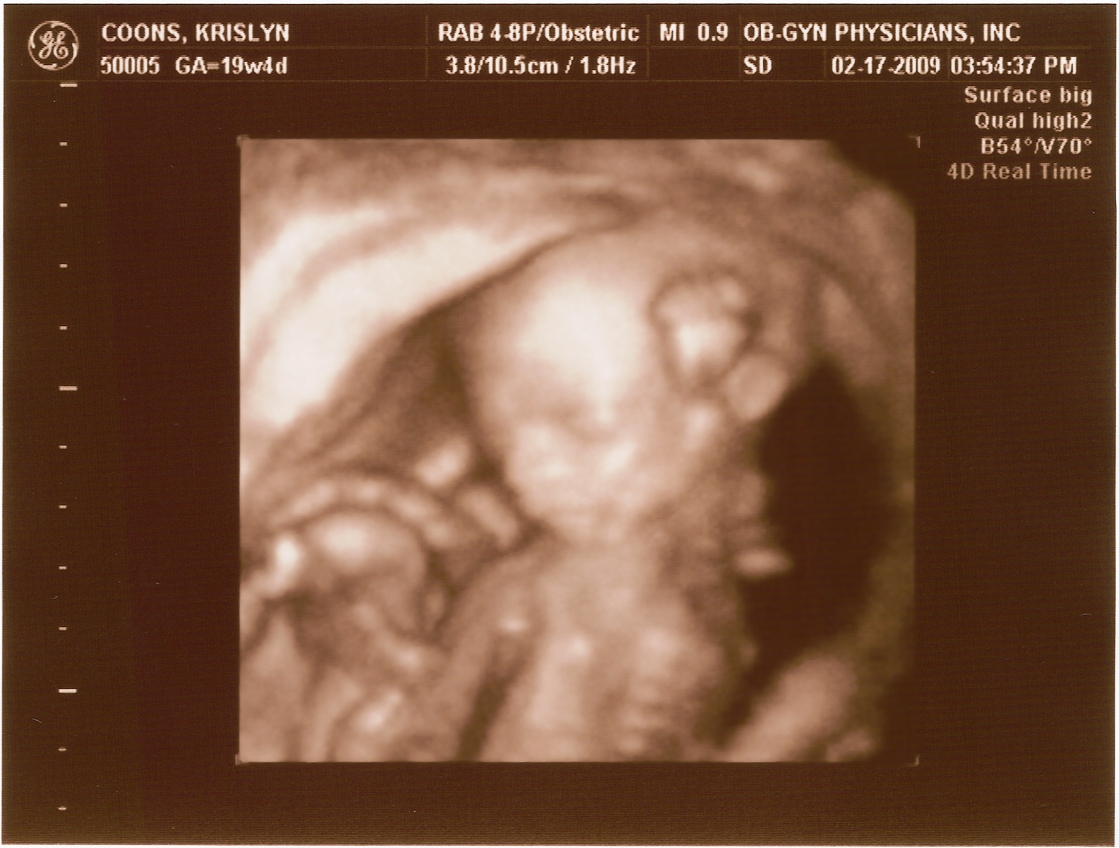

20 weeks -

Arm & Head

First ultrasound! The baby measures right on target and appears to be developing normally. All looked and sounded great. Krislyn is finally gaining some baby weight too!